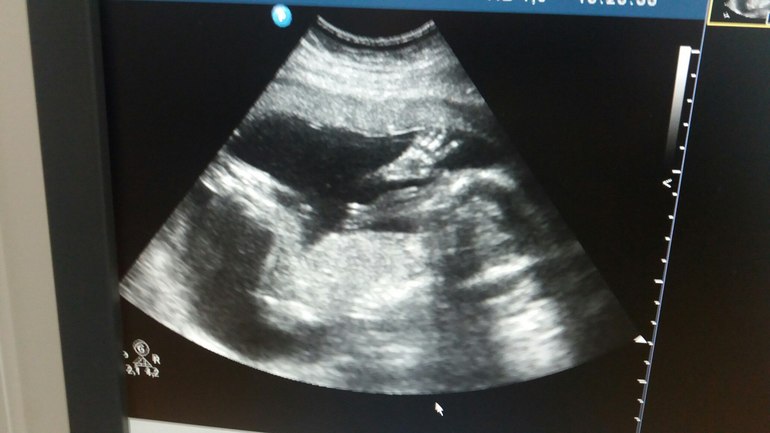

Второй скрининг, первый приветик от принцесы)))) и плацента 1ст зрелости

развиваемся и растем, по сроку у нас 20,1нед, да и по УЗИ не отстает, все показатели на 20-21 неделька, плацента поднялась на 2 см, и это уже радует, а главное нам сказали пол - у нас девочка))))) Так что кружочек перекрасился)))) И главное фотка с приветом от доченьки! Правда она у нас скромняшка, все время личико закрывала)))

Единственное смутила плацента 1 ст зрелости, хотя она должна быть до 24 нед -0, надеюсь это не критично

У меня тоже в 20 нед была плаценты 1 ст зрелости, на след УЗИ в 32 недели она так и осталось 1 ст зрелости. Так что не переживайте, просто это такой вариант работы плаценты видимо.